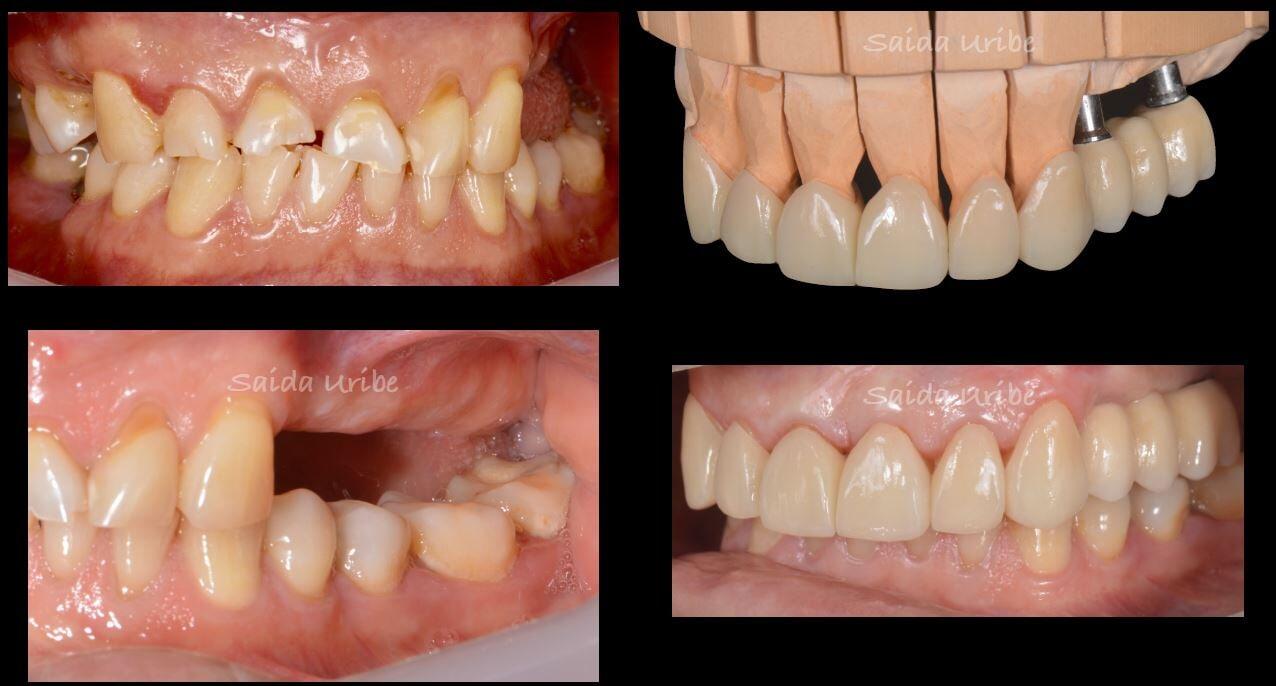

Un peridoncista es un dentista especializado en el cuidado de la salud de los tejidos de soporte del diente (hueso, encía, ligamento, cemento) y la sustitución de dientes perdidos por medio de implantes dentales. Se encarga de prevenir, diagnosticar y tratar las enfermedades periodontales y periimplantarias: gingivitis, periodontitis y periimplantitis principalmente.

La enfermedad periodontal afecta a millones de personas y es la causa principal de la perdida de piezas dentarias de la población adulta. Si la enfermedad es tratada en sus inicios tendrá un mejor pronóstico, por lo tanto, es importante acudir a cita de revisión con el dentista de manera preventiva o cuando se presenten alguno de los siguientes síntomas:

Un implante dental es una estructura cilíndrica parecida a un tornillo que se coloca quirúrgicamente en el hueso maxilar para sustituir la raíz de un diente. Una vez que el implante se integra al hueso, se fabrica una prótesis a medida que se coloca sobre este.

Los implantes mejoran la estética, la función masticatoria y tienen una tasa de éxito del 98%.